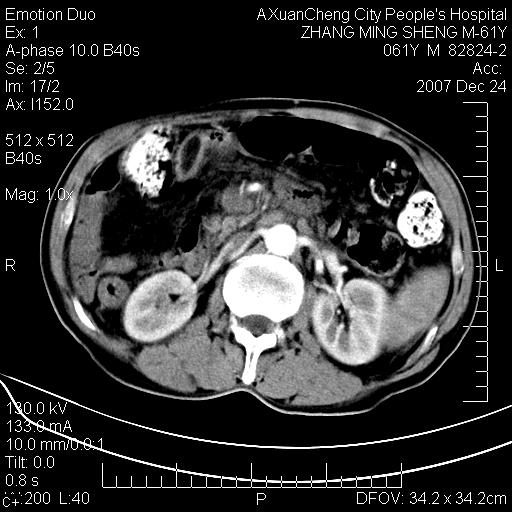

标题: CT11031:M61Y,胰腺占位

大家侃侃门静脉和胆管系统怎么回事,肝内转移?

胰腺癌肝转移

2,肝内多发结节状低密度占位,伴门脉及肠系膜上v栓子形成.考虑a;门脉及肠系膜上v血栓后肝改变.b;弥漫型肝癌伴门脉及肠系膜癌栓.

肝硬化,门脉高压,脾肿大;弥漫性肝癌,肝内、门脉、腹膜后淋巴结转移,肝内外胆管扩张,胰头区占位,建议mr检查

胰腺癌伴肝内转移;门脉、肠系膜上v癌栓形成。

考虑为:胰腺癌伴肝脏转移、腹膜后淋巴结转移,门静脉及肠系膜上静脉瘤栓形成。

胰体尾癌伴肝内转移,门静脉及肠系膜上静脉瘤栓形成.